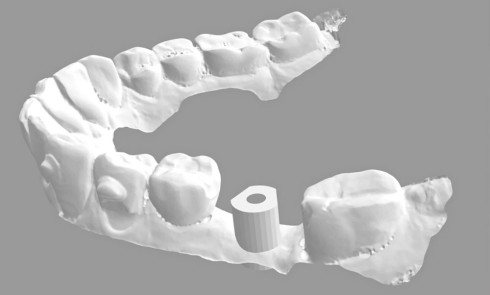

Une fois les transferts pick-up EV® transvissés, le porte-empreinte Tray, fenestré en regard des transferts, est chargé de matériau monophase Impregum™ Penta™ Soft (3M ESPE). Du matériau est déposé autour des transferts à l’aide d’une seringue. Après dévissage des transferts, ces derniers sont emportés dans l’empreinte et les analogues d’implants sont transvissés.

Une fois les transferts pick-up EV® transvissés, le porte-empreinte Tray, fenestré en regard des transferts, est chargé de matériau monophase Impregum™ Penta™ Soft (3M ESPE). Du matériau est déposé autour des transferts à l’aide d’une seringue. Après dévissage des transferts, ces derniers sont emportés dans l’empreinte et les analogues d’implants sont transvissés.

Une fois les transferts pick-up EV® transvissés, le porte-empreinte Tray, fenestré en regard des transferts, est chargé de matériau monophase Impregum™ Penta™ Soft (3M ESPE). Du matériau est déposé autour des transferts à l’aide d’une seringue. Après dévissage des transferts, ces derniers sont emportés dans l’empreinte et les analogues d’implants sont transvissés.

Une fois les transferts pick-up EV® transvissés, le porte-empreinte Tray, fenestré en regard des transferts, est chargé de matériau monophase Impregum™ Penta™ Soft (3M ESPE). Du matériau est déposé autour des transferts à l’aide d’une seringue. Après dévissage des transferts, ces derniers sont emportés dans l’empreinte et les analogues d’implants sont transvissés.

Une fois les transferts pick-up EV® transvissés, le porte-empreinte Tray, fenestré en regard des transferts, est chargé de matériau monophase Impregum™ Penta™ Soft (3M ESPE). Du matériau est déposé autour des transferts à l’aide d’une seringue. Après dévissage des transferts, ces derniers sont emportés dans l’empreinte et les analogues d’implants sont transvissés.